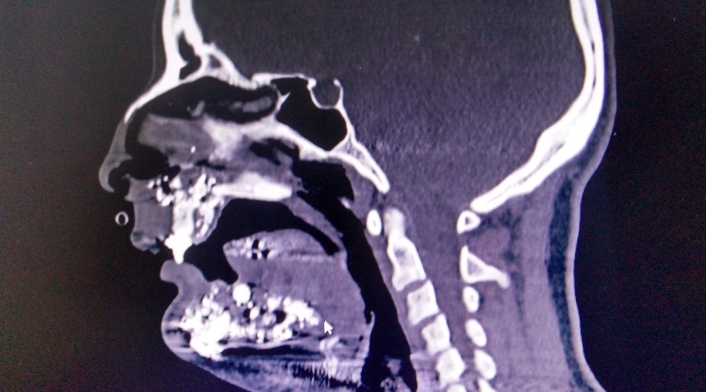

Se trata de María Marcela González, quien una vez recibió los impactos de bala, fue remitida al Hospital de Meissen en donde fue sometida a varias cirugías y a una completa reconstrucción facial que permitió que se salvara su vida milagrosamente.